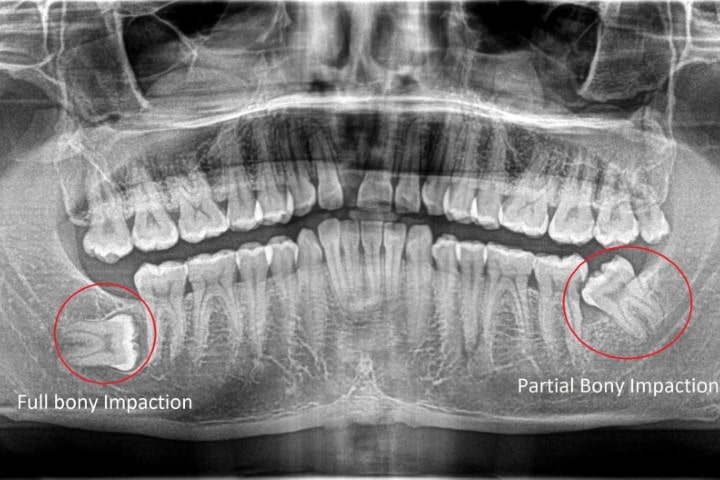

Răng khôn mọc lệch hay mọc ngầm có thể bị kẹt trong xương hàm, đè lên xương và các dây thần kinh xung quanh hoặc có thể bị xoắn. Răng khôn khi va chạm với các răng khác có thể dẫn đến sự xuất hiện của các u nang hay áp xe (một túi chất lỏng tích tụ và sẽ lây nhiễm sang khu vực lân cận) hoặc một khối u lành tính bên dưới răng, gây tổn thương xương hàm và hệ thống dây thần kinh quanh hàm. Nếu không nhổ răng kịp thời, răng khôn có thể làm xô lệch toàn hàm răng hoặc thậm chí là mất răng hàng loạt.